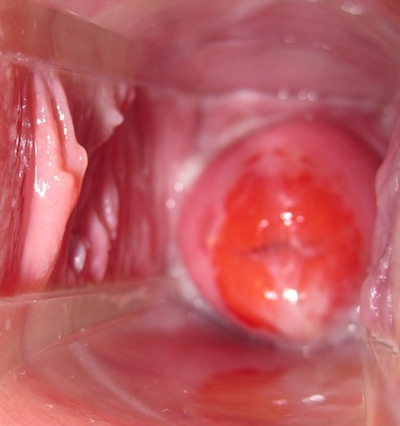

子宮頸癌圖片

宮頸癌

宮頸癌

宮頸癌

宮頸癌

宮頸癌

宮頸癌

宮頸癌

宮頸癌

宮頸癌

宮頸癌

宮頸癌

宮頸癌

宮頸癌

宮頸癌

宮頸癌

宮頸癌

宮頸癌

宮頸癌

宮頸癌

宮頸癌